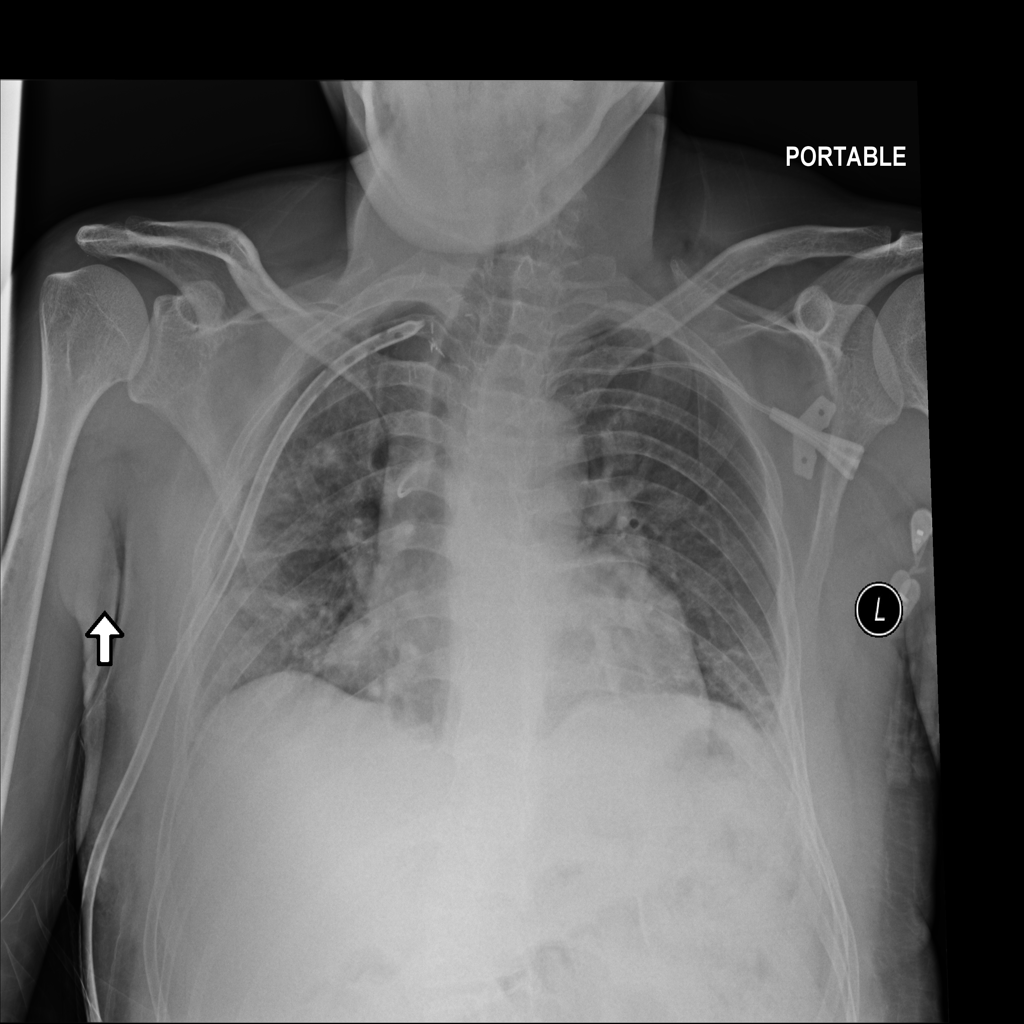

PAT-4639 · IMG-011Pneumothorax

PAT-4639 · IMG-011

AP